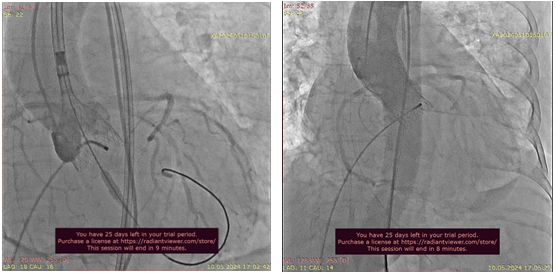

Ciddi aortal çatışmazlıqla bağlı kardiogen şok xəstədə TAVI